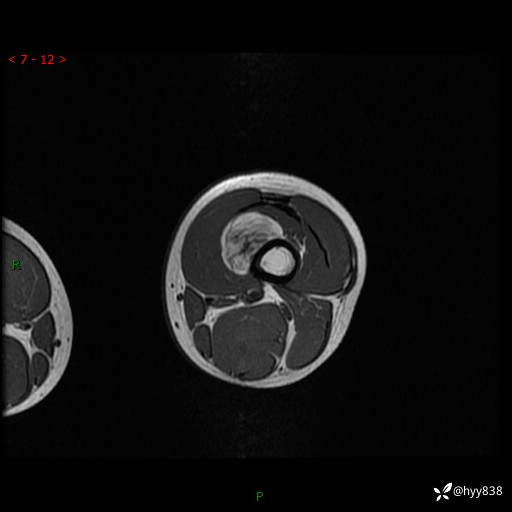

现病史:患儿3天前无意中被发现其左大腿有一包块,约鸡蛋大小,包块表面皮肤无红肿、触痛,无发热、破溃等,患儿家属当时未做特殊处理,经观察发现包块未见消退,今携患儿来我院就诊,门诊医师以“左大腿包块”收入院。 病程中,患儿神清,精神可,饮食睡眠正常,大小便通畅,体力体重无明显改变。

左大腿MRI平扫+增强